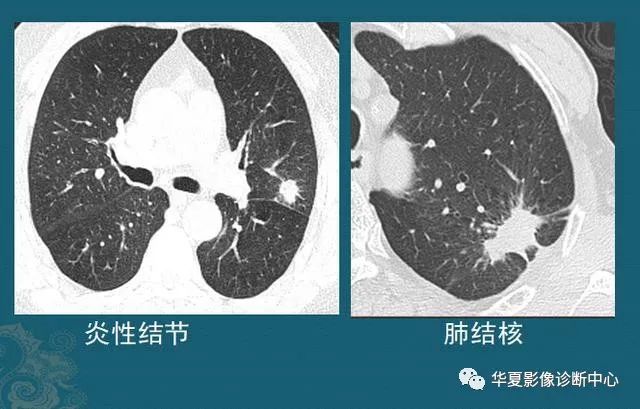

最后给大家看几个手术成功的肺结节,有个直径超过3 cm,已经属于肿块了(红箭头是肿瘤,蓝箭头是手术瘢痕):

病例1,女性,52岁,咳嗽、发热,胸部检查发现1.3 cm肺结节,手术病理为肺腺癌:

病例2,男性,75岁,体检发现左肺结节,2.9 cm,左肺下叶切除5年(病理类型不详,在外院手术,家属只记得是肺癌,不能描述具体类型,看肿瘤形态,鳞癌、腺癌都有可能):

病例3,女性,61岁,胸闷一周查出肺癌,3.5 cm,有分叶、胸膜牵拉,并且已经侵犯局部脏层胸膜,手术后病理是肺腺癌: